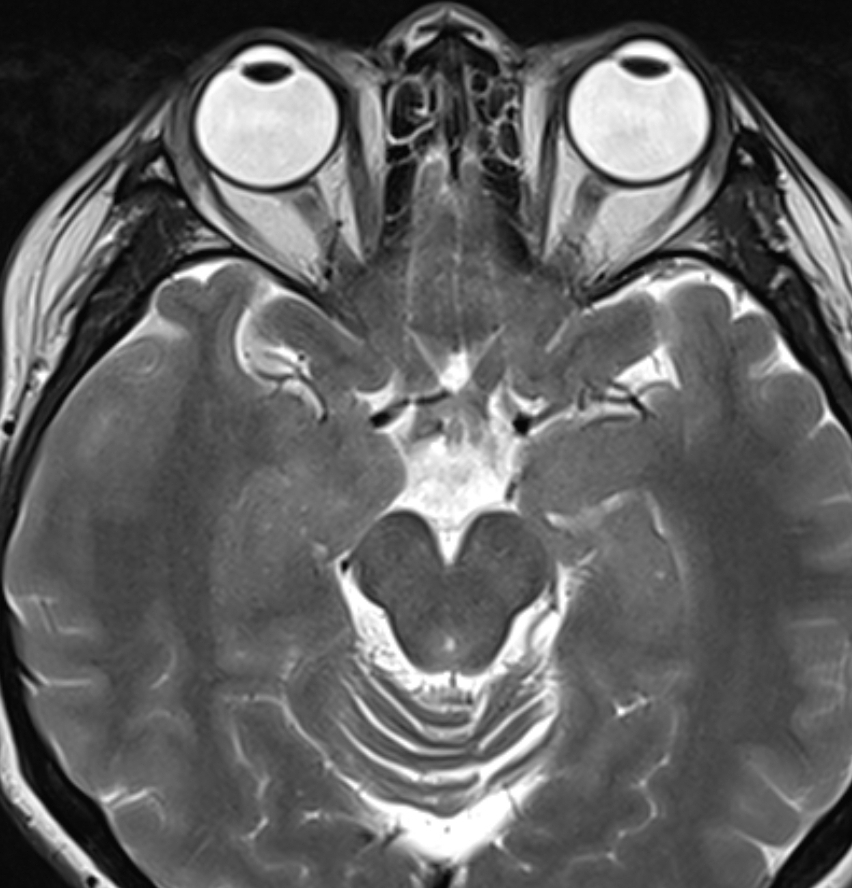

For some weeks ago, the EENT (ears, eyes, nose and throat) specialist referred me to an MRI examination of my brain and my temporal bone. It’s because I’ve been experiencing sudden dizziness/vertigo. The specialist wanted to rule out cancer and other form of diseases in my head because she haven’t seen anything wrong with me during the appointment. As we all know, the vestibular system is responsible for the sense of balance and any damage or sickness in that area can affect our balance and can result to for instance vertigo, hearing loss and etc.

Then when the examination’s done, it was time for the waiting game. Which is worst. It makes me think that my case is so bad that the radiologist had to take time looking at my MRI. I’m sure others can relate. Even though it only takes 3-5 days for the result to come, I’ve got really impatient that I actually asked the AI app to describe my MRI photo that I got the same day of the examination. And guess what, it said that it seems like I had a cyst! So of course I got a bit shocked but at the same time sceptical. So I just set it aside and distracted to avoid inducing anxiety.